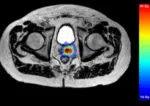

PET-based online adaptive radiotherapy is currently only in use in research and in some clinical trials. A study by Li et al [15] investigated the clinical feasibility of PSMA-PET imaging in adaptive SABR workflows for high-risk prostate cancers. The study supported the use of biology-guided radiotherapy when implemented using standard ART platforms such as MR-Linac and CBCT-based treatment machines. They expressed clear benefits the PET-image can bring, extending beyond anatomical landmarks to using actual biomarkers of the patient to plan treatment [15]. The downside to PET-based adaptive radiotherapy is the need for daily preparatory injections of an expensive radioactive tracer 45 to 60 minutes before treatment thereby tripling to quadrupling the average session time to the patient. The radiotracer also adds whole-body dose burden larger than that of CT and these systems also require a CT to help interpret the PET scans.